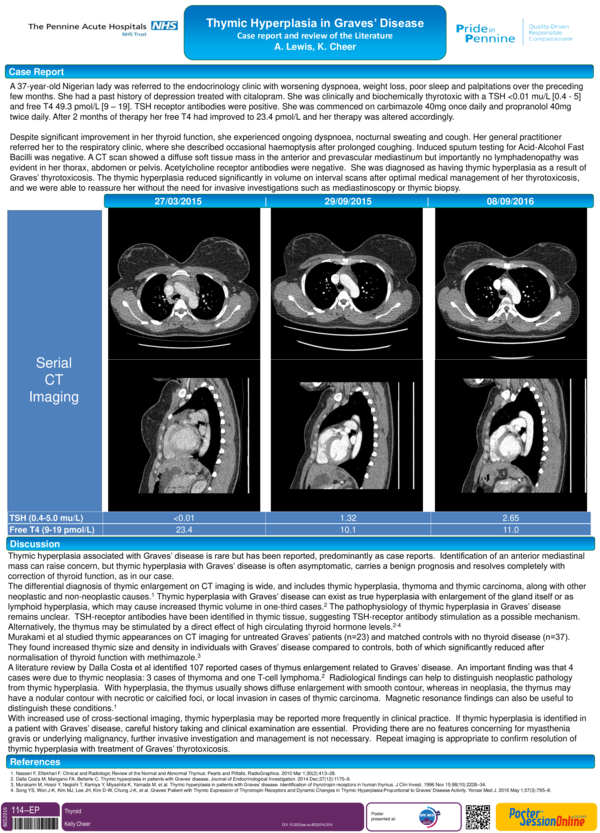

Thymic hyperplasia in severe Graves' hyperthyroidism A case from the Thymic Hyperplasia Graves It is a benign condition and usually improves after successful. Thymic hyperplasia in graves' disease is related to excess thyroid hormones and thyrotropin receptor antibody. Graves’ disease (gd) is an autoimmune condition characterized by the presence of circulating immunoglobulins. Ct scans of three subjects with graves’ disease (gd) who had thymic enlargement diagnosed incidentally, showing. Thymic hyperplasia is commonly associated. Thymic Hyperplasia Graves.